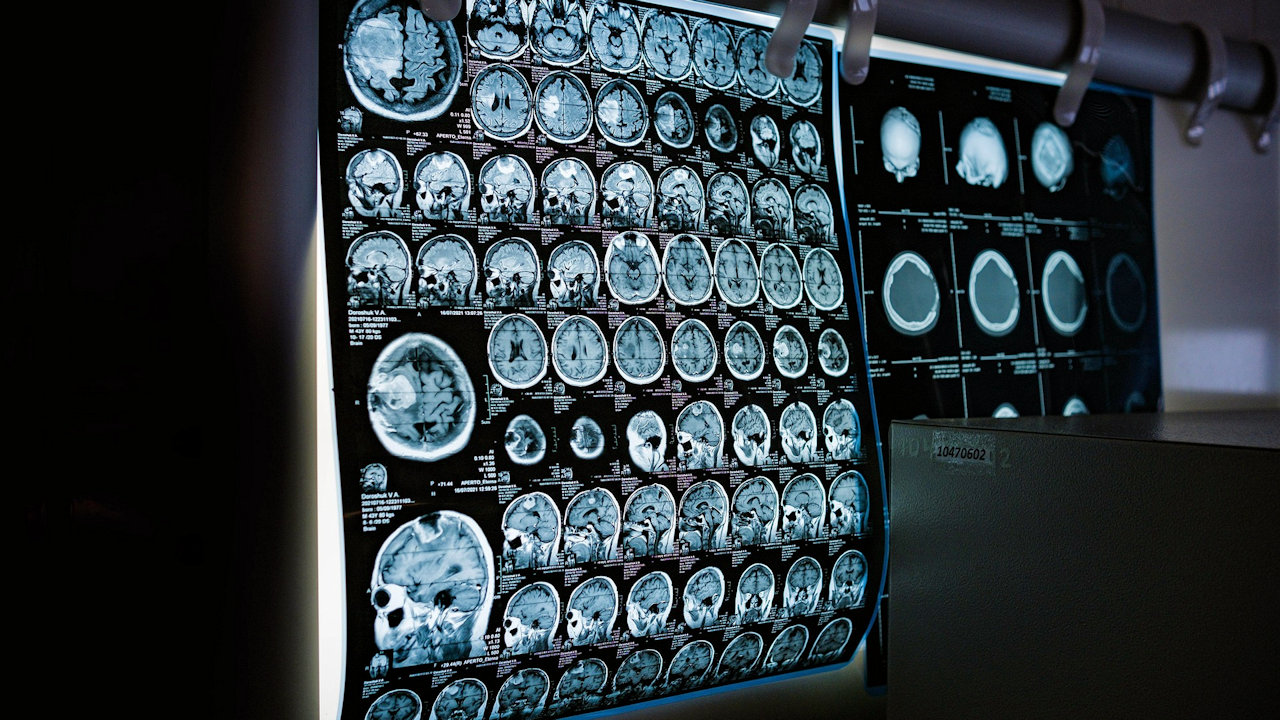

Die MIDAS-Studie untersuchte Wirksamkeit digitaler, klinischer Entscheidungshilfen für medizinische Bildgebung. (Quelle: Dmitriy Gutarev/Pixabay)

Medizinische Bildgebung ist ein essenzieller Bestandteil der modernen Gesundheitsversorgung. Durch fortschrittliche Technologien wie Computer- und Kernspintomographie lassen sich Erkrankungen früher und präziser diagnostizieren. Gleichzeitig führt der vermehrte Einsatz dieser Verfahren zu einer exponentiellen Zunahme von Untersuchungen, die nicht immer medizinisch notwendig sind. Dies kann zu vermeidbarer Strahlenexposition, längeren Wartezeiten, höheren Kosten und zusätzlicher Belastung des medizinischen Personals führen.

Klinische Entscheidungsunterstützungssysteme (Clinical Decision Support Systems, CDSS) sollen durch Echtzeit-Feedback Ärzten bei der Auswahl geeigneter Verfahren oder Therapieansätze unterstützen. Trotz vielversprechender Ansätze blieb die Akzeptanz im klinischen Alltag bisher gering. Die MIDAS-Studie untersuchte daher, ob ein solches System speziell für die Anforderung von Bildgebungsverfahren in Universitätskliniken sinnvoll eingesetzt werden kann. In der Studie zeigte eine Ampel der Ärztin oder dem Arzt an, ob die gewählte Bildgebung zum Krankheitsbild passt.